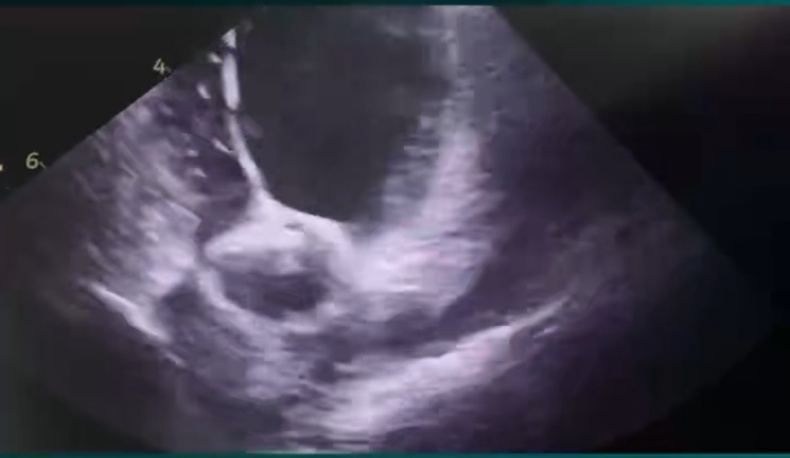

72岁的陈大爷因“反复活动后心累、气促”入院,心电图确诊为:全心增大 三尖瓣反流(重度)二尖瓣反流(中度)左室收缩功能测值减低,少量心包积液,CHA₂DS₂-VASc评分5分(高危),HAS-BLED评分3分(出血高风险)。经多学科评估,患者房颤药物控制效果差,且因既往消化道出血史,无法长期耐受抗凝治疗。为同时解决房颤症状及卒中预防难题,心血管内科团队及DSA介入治疗医学中心决定采用“射频消融+左心耳封堵”一站式手术方案。 术前,介入手术室联合心血管内科、麻醉手术中心、超声医学科、重症医学科等多学科团队,依托Carto三维电解剖标测系统及心腔内超声(ICE)技术,全面重建患者心脏结构,精准定位肺静脉及左心耳。

团队率先为患者实施全麻下房颤射频消融术,随后,经ICE实时引导,将Watchman FLX封堵器精准释放在左心耳开口处,术后造影及超声验证封堵完全无残余分流。

Carto三维系统结合ICE技术,既能提升消融精准度、降低并发症,又可动态评估左心耳形态,确保封堵器完美贴合,尤其适用于左心耳结构复杂或需个体化治疗的患者。